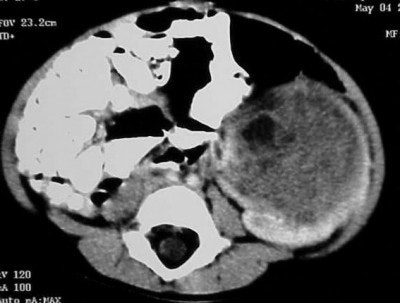

Axial images (Figures CT 10 and CT 11) show a mass beginning just below the kidneys on the left side and extending almost through the pelvis. The child was diagnosed with Wilm’s tumor of the left kidney.

![]() |

| Figure CT 10 |

| Figure CT 11 |

She underwent a left nephrectomy and chemotherapy and recovered well.